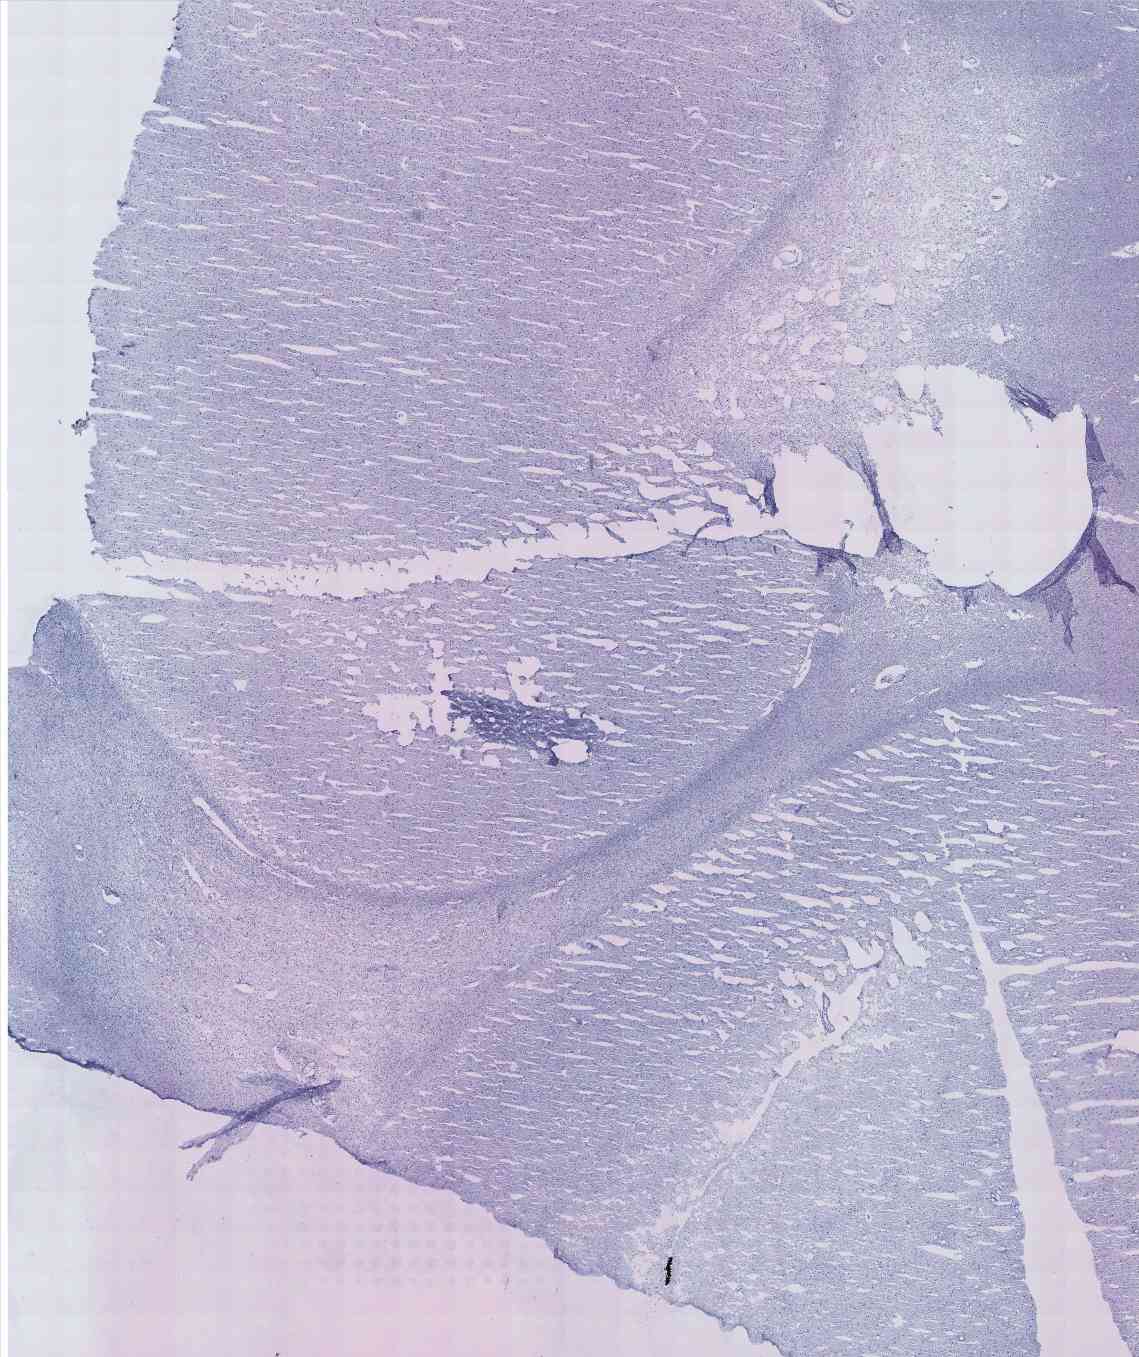

Chip 021 Well E1